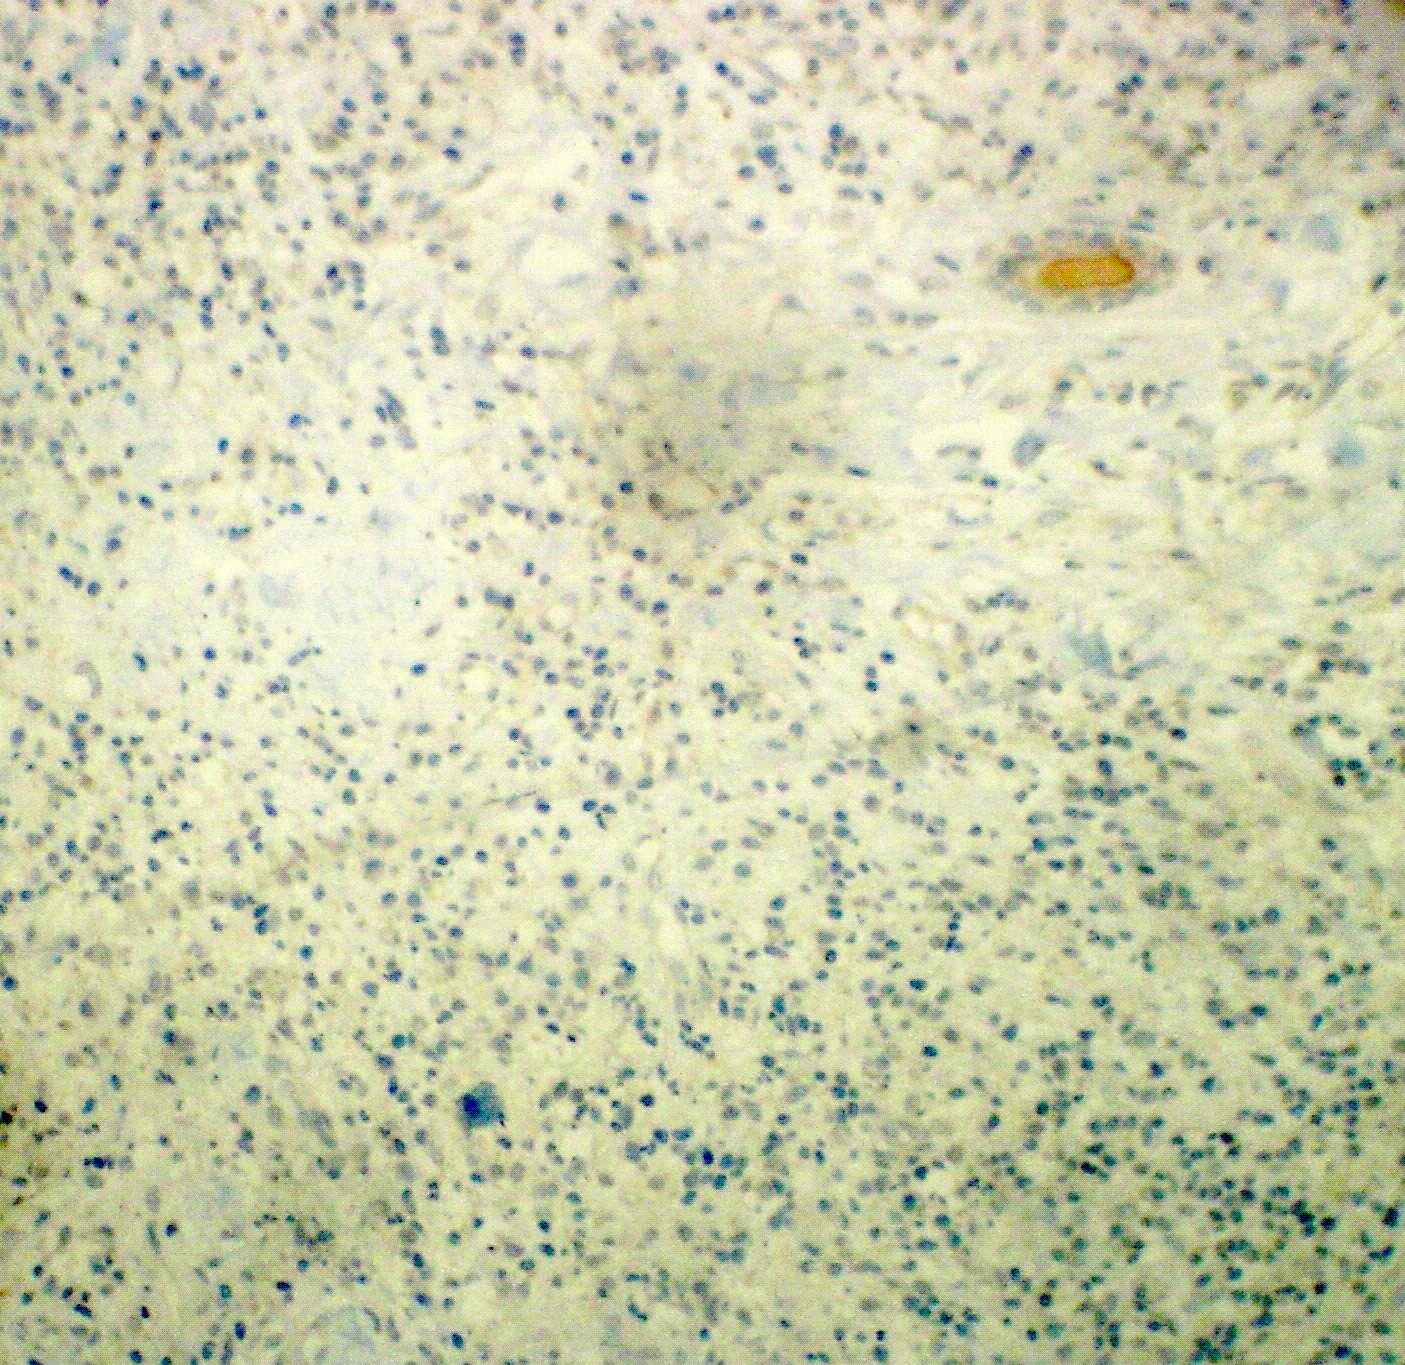

Fig 8: ALK-1 immunohistochemical stain showed negative staining for all cells [X 160].